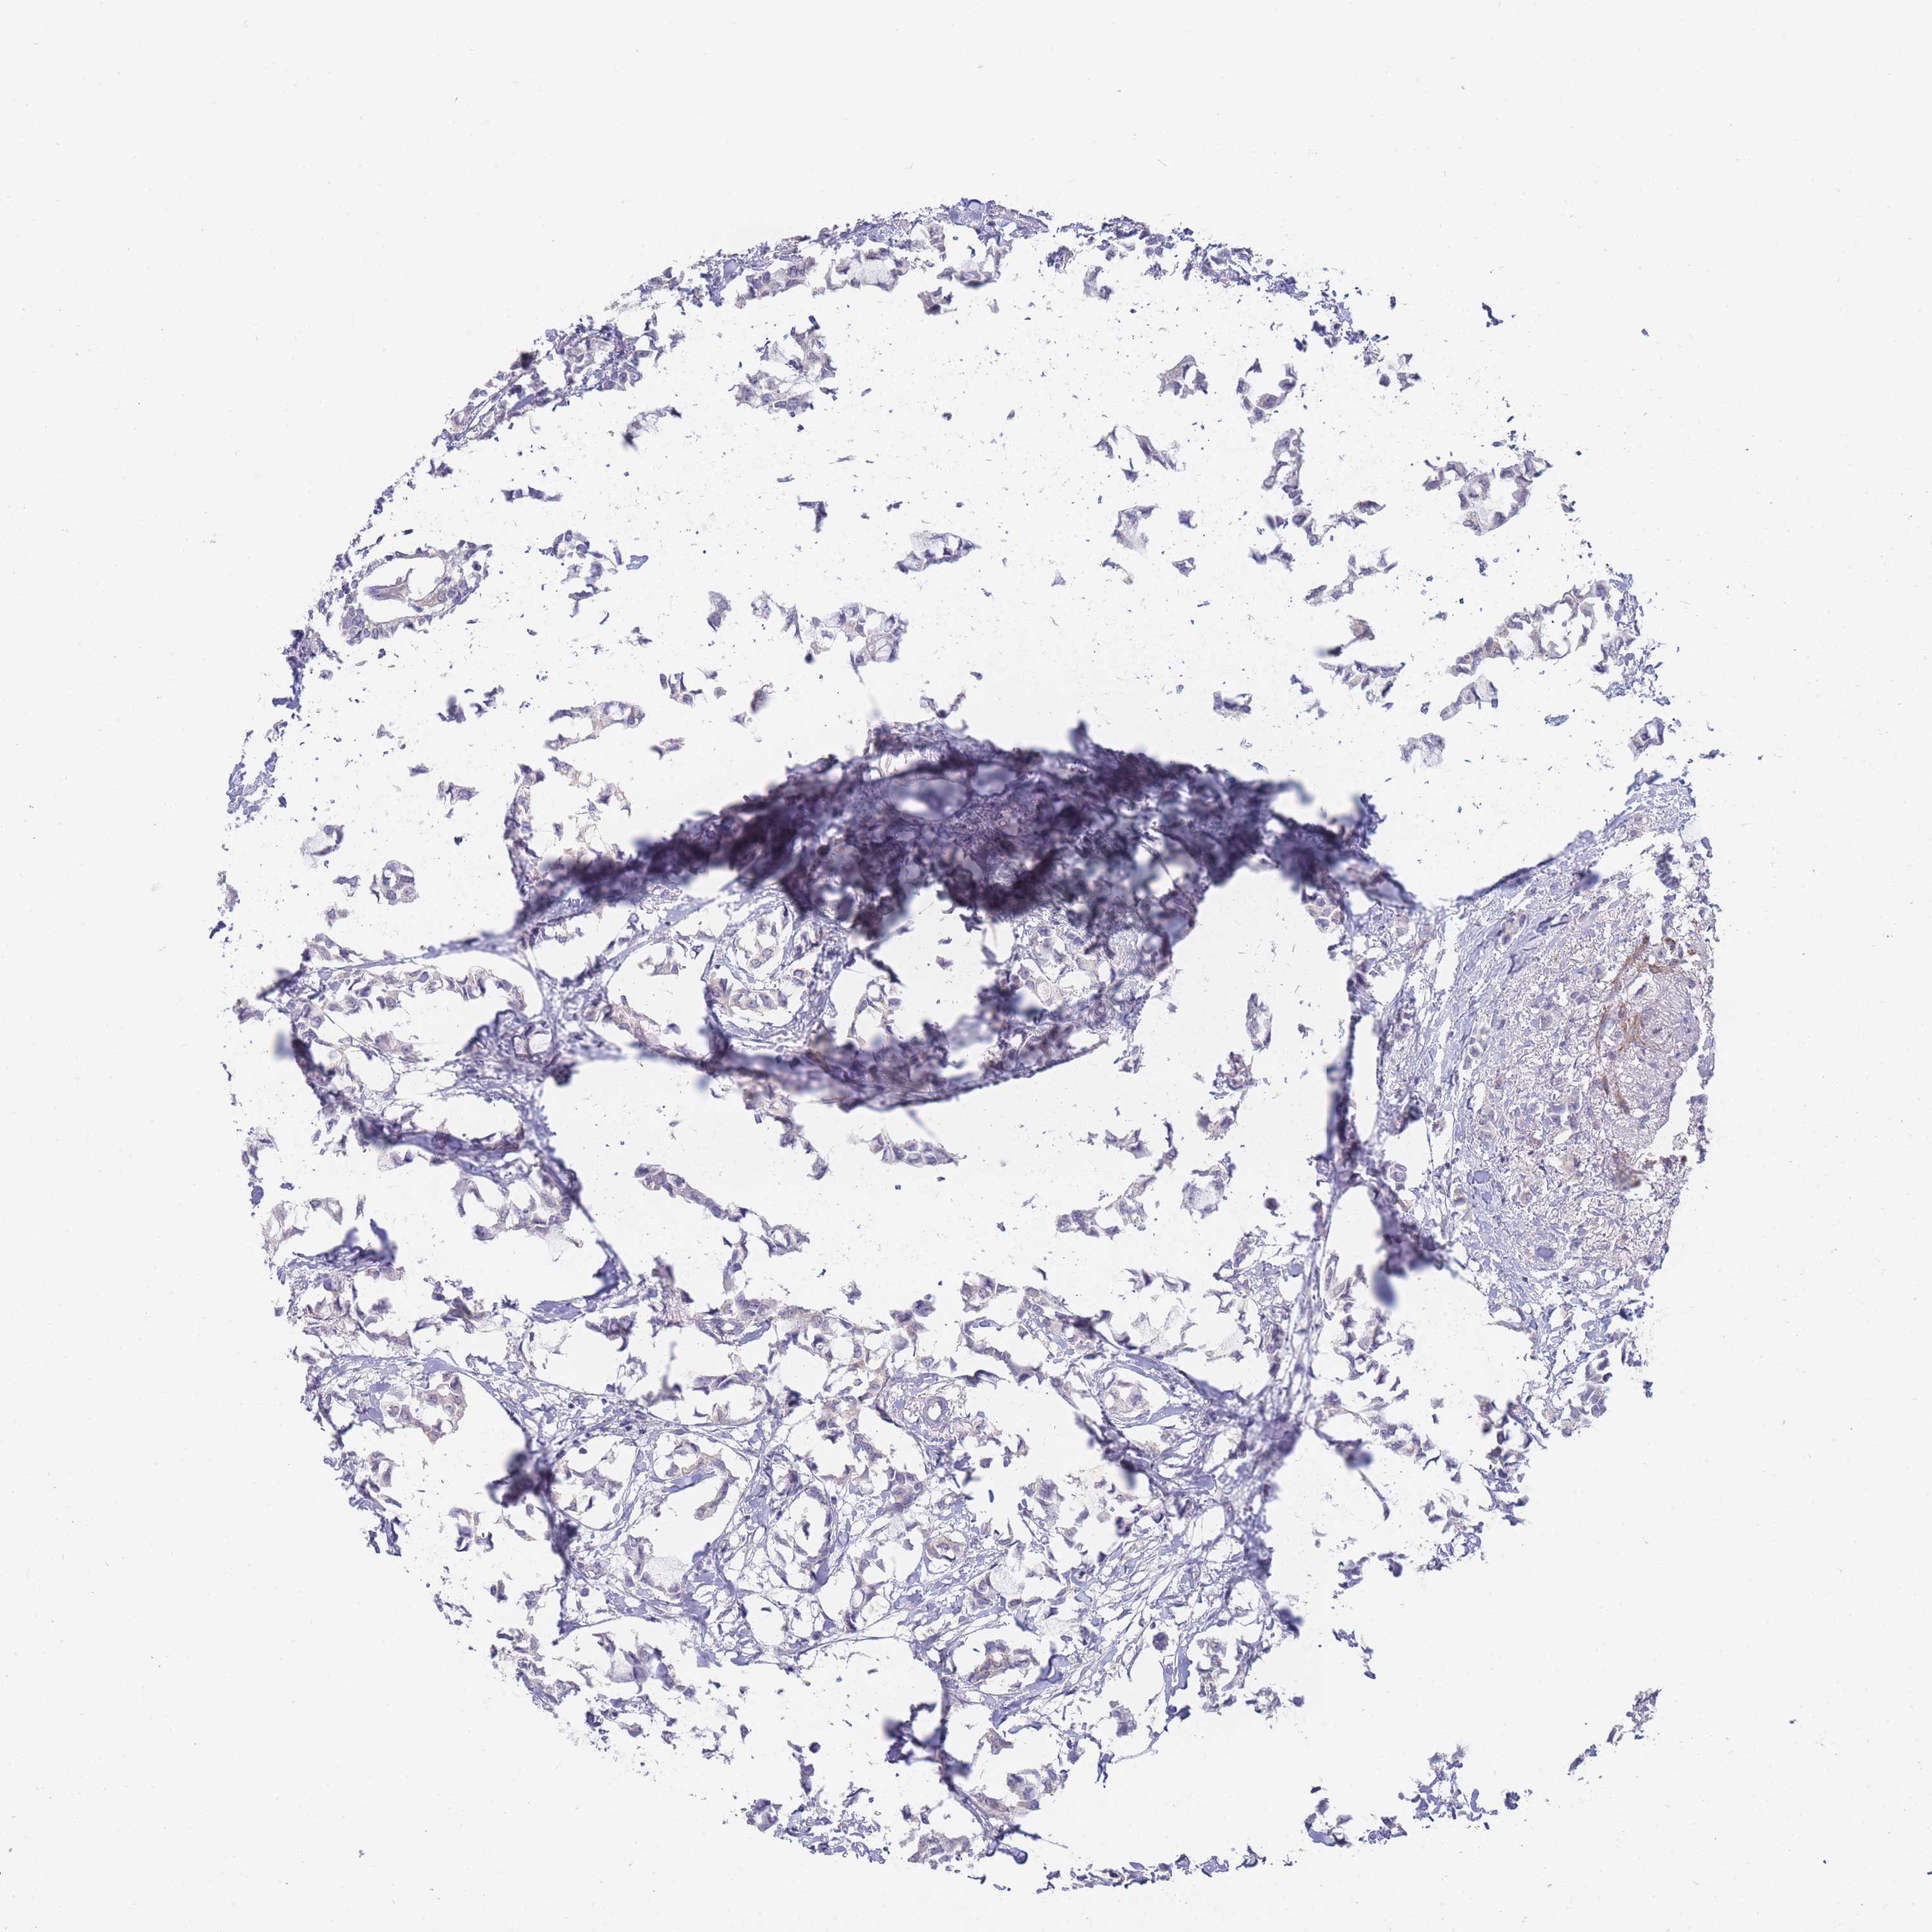

CANCER BREAST CANCER Show tissue menu

BRCA TCGA BRCA VALIDATION PROTEIN EXPRESSION